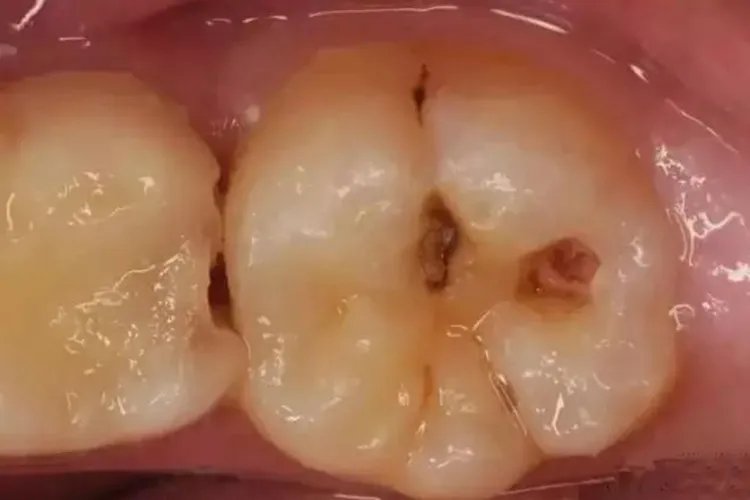

概述大牙虫牙指龋病,会使牙釉质表面缺损,由白垩色发展为黄褐色,有时会感到明显疼痛,多由于口腔环境较差引起,可以进行药物治疗。症状大牙虫牙指龋病,龋病患者的病损集中于牙体硬组织,包括牙釉质、牙本质和牙骨质,具体可以分为浅龋、中龋、深龋。浅龋龋坏限于釉质或牙骨质,牙面呈白垩色或黑色着色,局部粗糙,一般无自觉症状,对冷、热、酸、甜等刺激无明显反应。

中龋龋坏侵入牙本质浅层,有龋洞形成,牙本质呈黄褐至深褐色,可有冷、热、酸、甜激发痛和探痛,刺激消失时症状也消失。

深龋龋坏侵入牙本质深层,但未穿髓,龋洞深大,无自发痛,龋洞中有食物嵌入或者病牙遇冷、热、化学刺激时会出现疼痛,刺激消失症状消失。